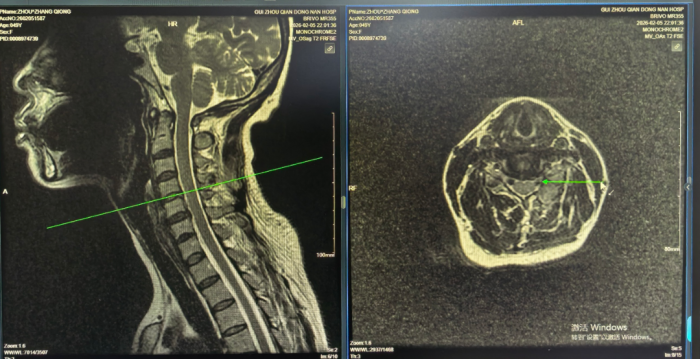

术后复查